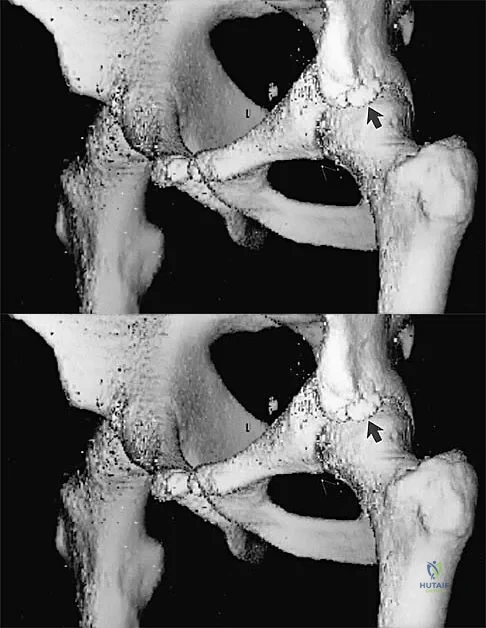

Question 32

A 24-year-old rugby player presents for management of recurrent anterior shoulder instability. He has had four dislocations. Computed tomography (CT) with 3D sagittal reconstruction demonstrates an anteroinferior glenoid bone loss of 22% and a large, engaging Hill-Sachs lesion. Based on current literature and evidence-based treatment algorithms, which of the following is the most appropriate surgical management?